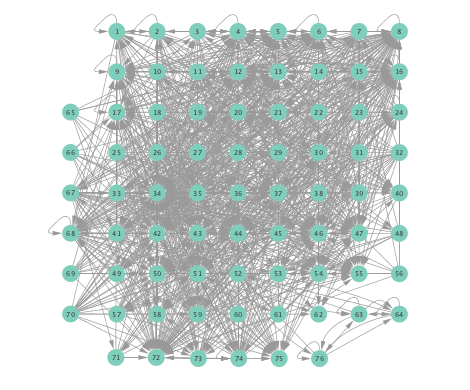

Figure 2 depicts networks inferred from different algorithms for both preictal and ictal intervals of the time series. The figure illustrates results obtained by the linear SVARM, and the K-SVARM approach with and without kernel selection. Each node in the network is representative of an electrode, and it is depicted as a circle, while the node arrangement is forced to remain consistent across the four visual representations. A cursory inspection of the visual maps reveals significant variations in connectivity patterns between ictal and preictal intervals for both models. Specifically, networks inferred via the K-SVARMs, reveal a global decrease in the number of links emanating from each node, while those inferred via the linear model depict increases and decreases in links connected to different nodes. Interestingly, the K-SVARM with kernel selection recovered most of the edges inferred by the linear and the K-SVARM using a polynomial kernel, which implies that both linear and nonlinear interactions may exist in brain networks. Clearly, one is unlikely to gain much insight only by visual inspection of the network topologies. To further analyze differences between inferred networks from both models, and to assess the potential benefits gained by adopting the novel scheme, several network topology metrics are computed and compared in the next subsection.